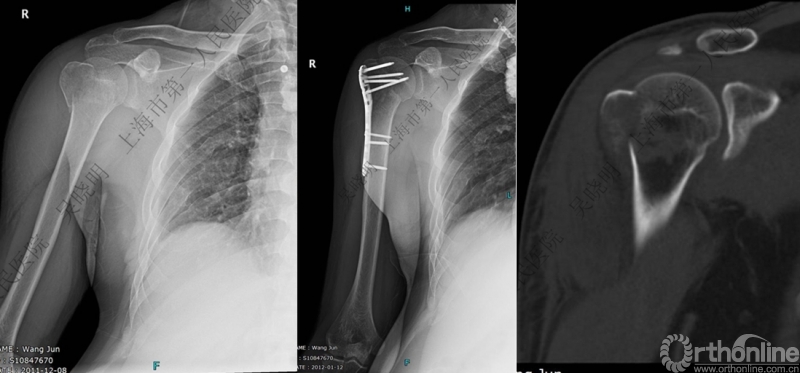

伴大结节骨折的老年性肩关节前脱位伴肱骨头外翻

肩关节前脱位合并大结节骨折&肱骨头外翻:外翻压缩型(Neer 分型)

对这型骨折进行手法复位会导致肱骨头和肱骨干之间的连续性消失。肱骨头和肱骨干之间连续性尚存,肱骨头前脱位(Robsion 3b)

外翻压缩型肱骨近端骨折

钢板固定

X线是孤立性向下移位的大结节,一定要小心,多伴有肱骨外科颈骨折

全麻下闭合复位,钢板固定